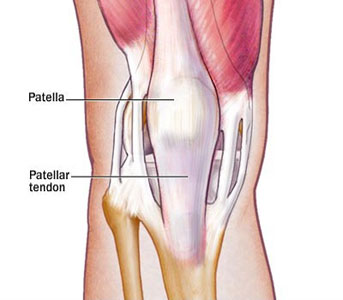

What is Patella Fracture Patella Dislocation

Patella Fractures

Patella Fractures Broken Kneecap of the Knee Knee Specialist

Patellar Fractures Physiopedia